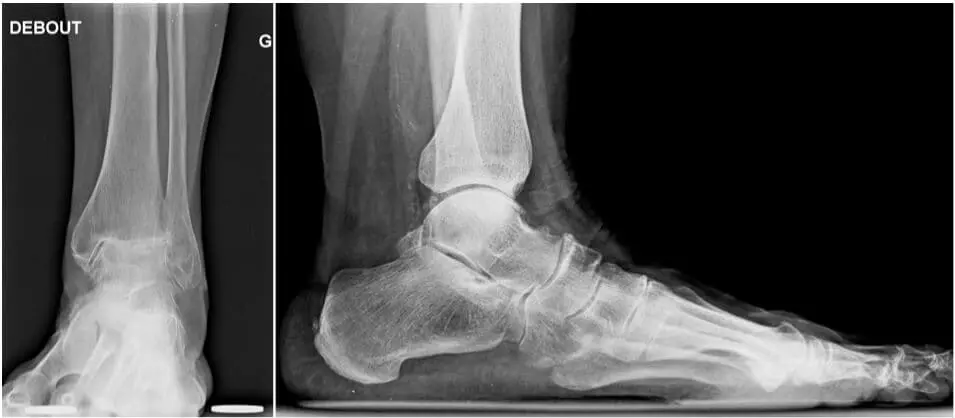

Osteoarthritis can be defined as the presence of degenerative lesions, wear and local or generalized reduction and/or loss of cartilage at the level of a joint. Several mechanical causes may lead to this: repeated sprains, instability, experienced fractures, osteochondral injuries… On radiographs, we can see an asymmetric narrowing of the joint space, a condensation of the underlying bone, formation of bone growth, cyst formation,….

In case of arthritis, there is a more homogeneous destruction of the cartilage, by, often, autoimmune disorders such as rheumatoid arthritis, psoriasis,… This almost always means that the capsule is weaker and of lower quality as a result of which it is sometimes difficult to preserve the mobility of the joint. A choice must then be made between an increased risk of recurrence versus performing an arthrodesis. On radiographs, the joint space is more symmetrically affected.

Arthrodesis: In advanced cases of osteoarthritis or arthritis, this remains seen as the gold standard treatment. The joint is fixed into its neutral position by means of open surgery or arthroscopy. The advantages are that it is a very reliable operation with clearly positive results over the years, and that it is a single procedure. Disadvantages are the prohibition to lean on the ankle and a plaster for 2 months after the operation, but mainly the fact that after an indefinite period (20-30 years), degenerative disorders may occur in the adjacent joints. These should take over part of the mobility of the ankle.